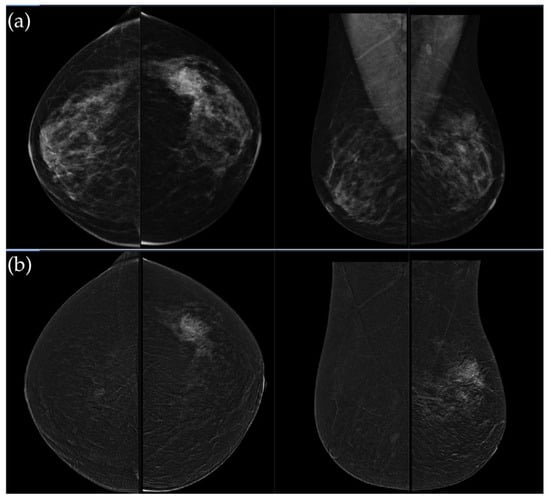

Figure 3. (a) Standard craniocaudal (CC) and mediolateral oblique (MLO) low-energy views reveal an irregular, spiculated mass of the left breast. The right breast shows a histopathologically confirmed fibroadenoma with dystrophic calcifications. (b) Recombined contrast-enhanced images (CC and MLO views) demonstrate early, complete heterogeneous enhancement. No pathologically enhancing axillary lymph nodes are detected. Histopathological analysis confirmed Luminal A breast carcinoma.

Figure 4. (a) Standard CC and MLO low-energy views reveal an irregular, spiculated mass with associated retraction of Cooper’s ligaments in the upper outer quadrant of the left breast. No suspicious microcalcifications are seen. The right breast appears unremarkable. (b) Recombined contrast-enhanced images (CC and MLO views) demonstrate an irregular, non-circumscribed lesion in the upper outer quadrant of the left breast with rapid early heterogeneous enhancement. Partially visualized axillary conglomerate on the left also demonstrates heterogeneous contrast enhancement in the early phase. Contralateral axilla is unremarkable. Histopathological analysis confirmed a Luminal B breast carcinoma.